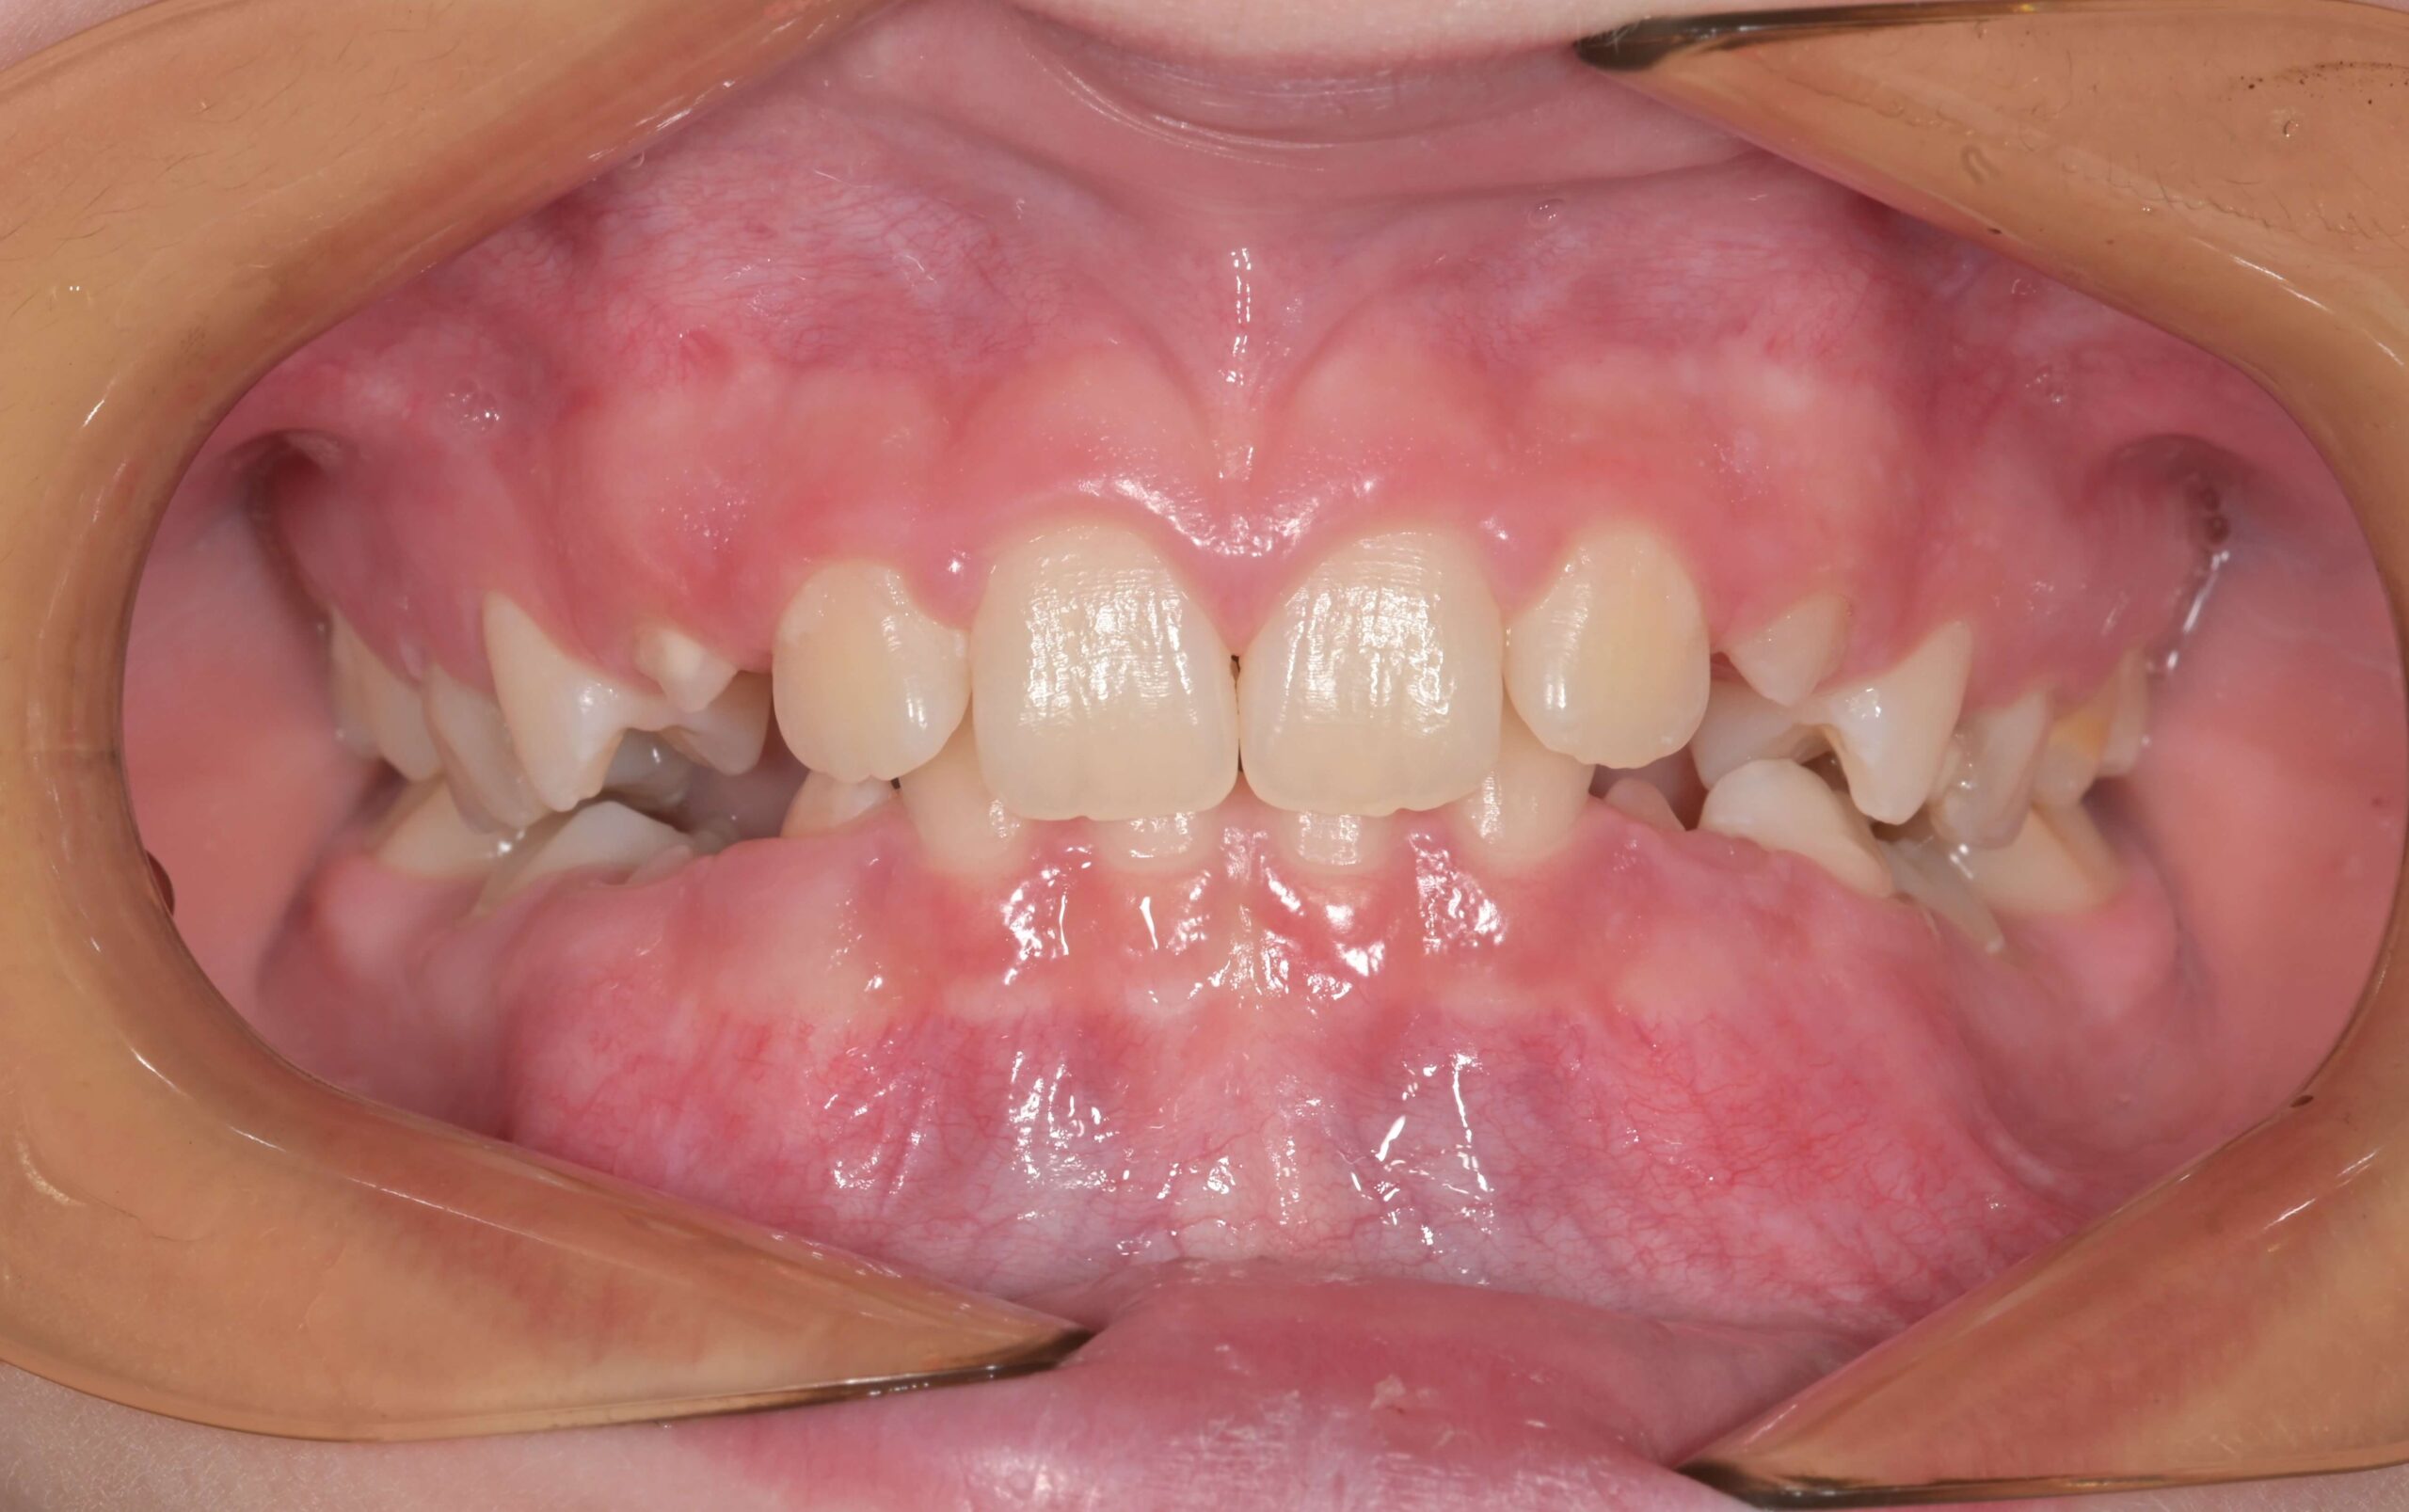

Съдържание Какво представлява дълбоката захапка? Дълбоката захапка е вид малоклузия, при която горните предни зъби значително припокриват долните предни зъби, когато моларите са затворени. Дълбоката захапка е най-често срещания вид неправилна захапка. Много хора подценяват този проблем, който може да бъде решен с правилно ортодонтско лечение. Защо дълбоката захапка трябва да бъде коригирана? Ето до […]